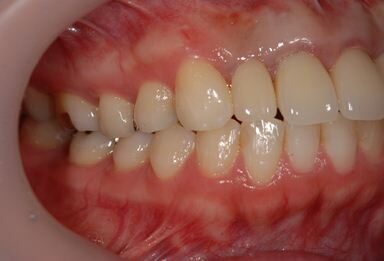

治療前

• 治療前